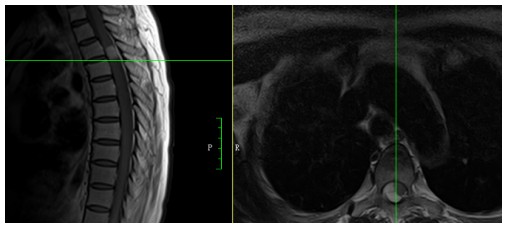

59歲鄒阿姨術(shù)前胸椎MRI檢查